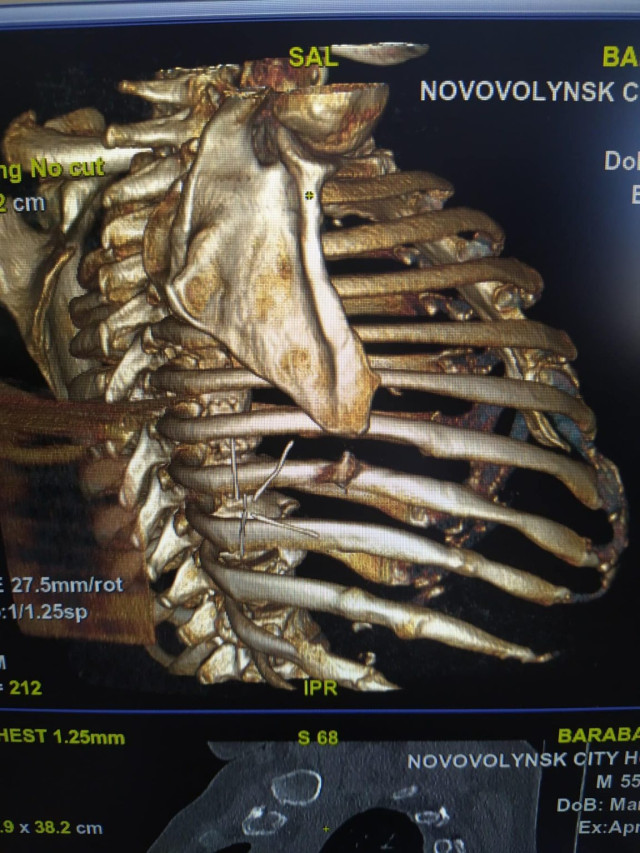

У Комунальне некомерційне підприємство «Нововолинська центральна міська лікарня» звернувся пацієнт - переселенець із Донецької області із мінно-вибуховим осколковим пораненням грудної клітки.

Сторонні тіла виявили під час КТ обстеження та провели оперативне втручання.

З грудної стінки лікарі видалили металевий осколок ( 2,0*1,0см) та шматки асфальту. Чоловіку пощастило, адже життєво важливі органи не заділо. Після оперативного втручання він почуває себе добре.